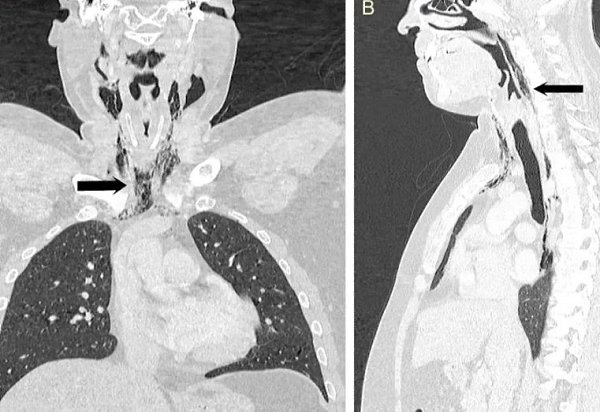

Мужчина испытал болезненные ощущения в области шеи, когда пытался сдержать чихание.

В результате чихания он ощутил «хлопок» в шее, после чего возникли проблемы с глотанием. МРТ-исследование показало, что воздух выходил через отверстие в трахее в мягкие ткани шеи. В течение нескольких дней мужчина получал питание через зонд, чтобы ткани могли зажить.

Когда мы сдерживаем чихание, воздух не может выйти наружу, и его давление разрывает мягкие ткани, причиняя им вред. Новая фобия в копилку.